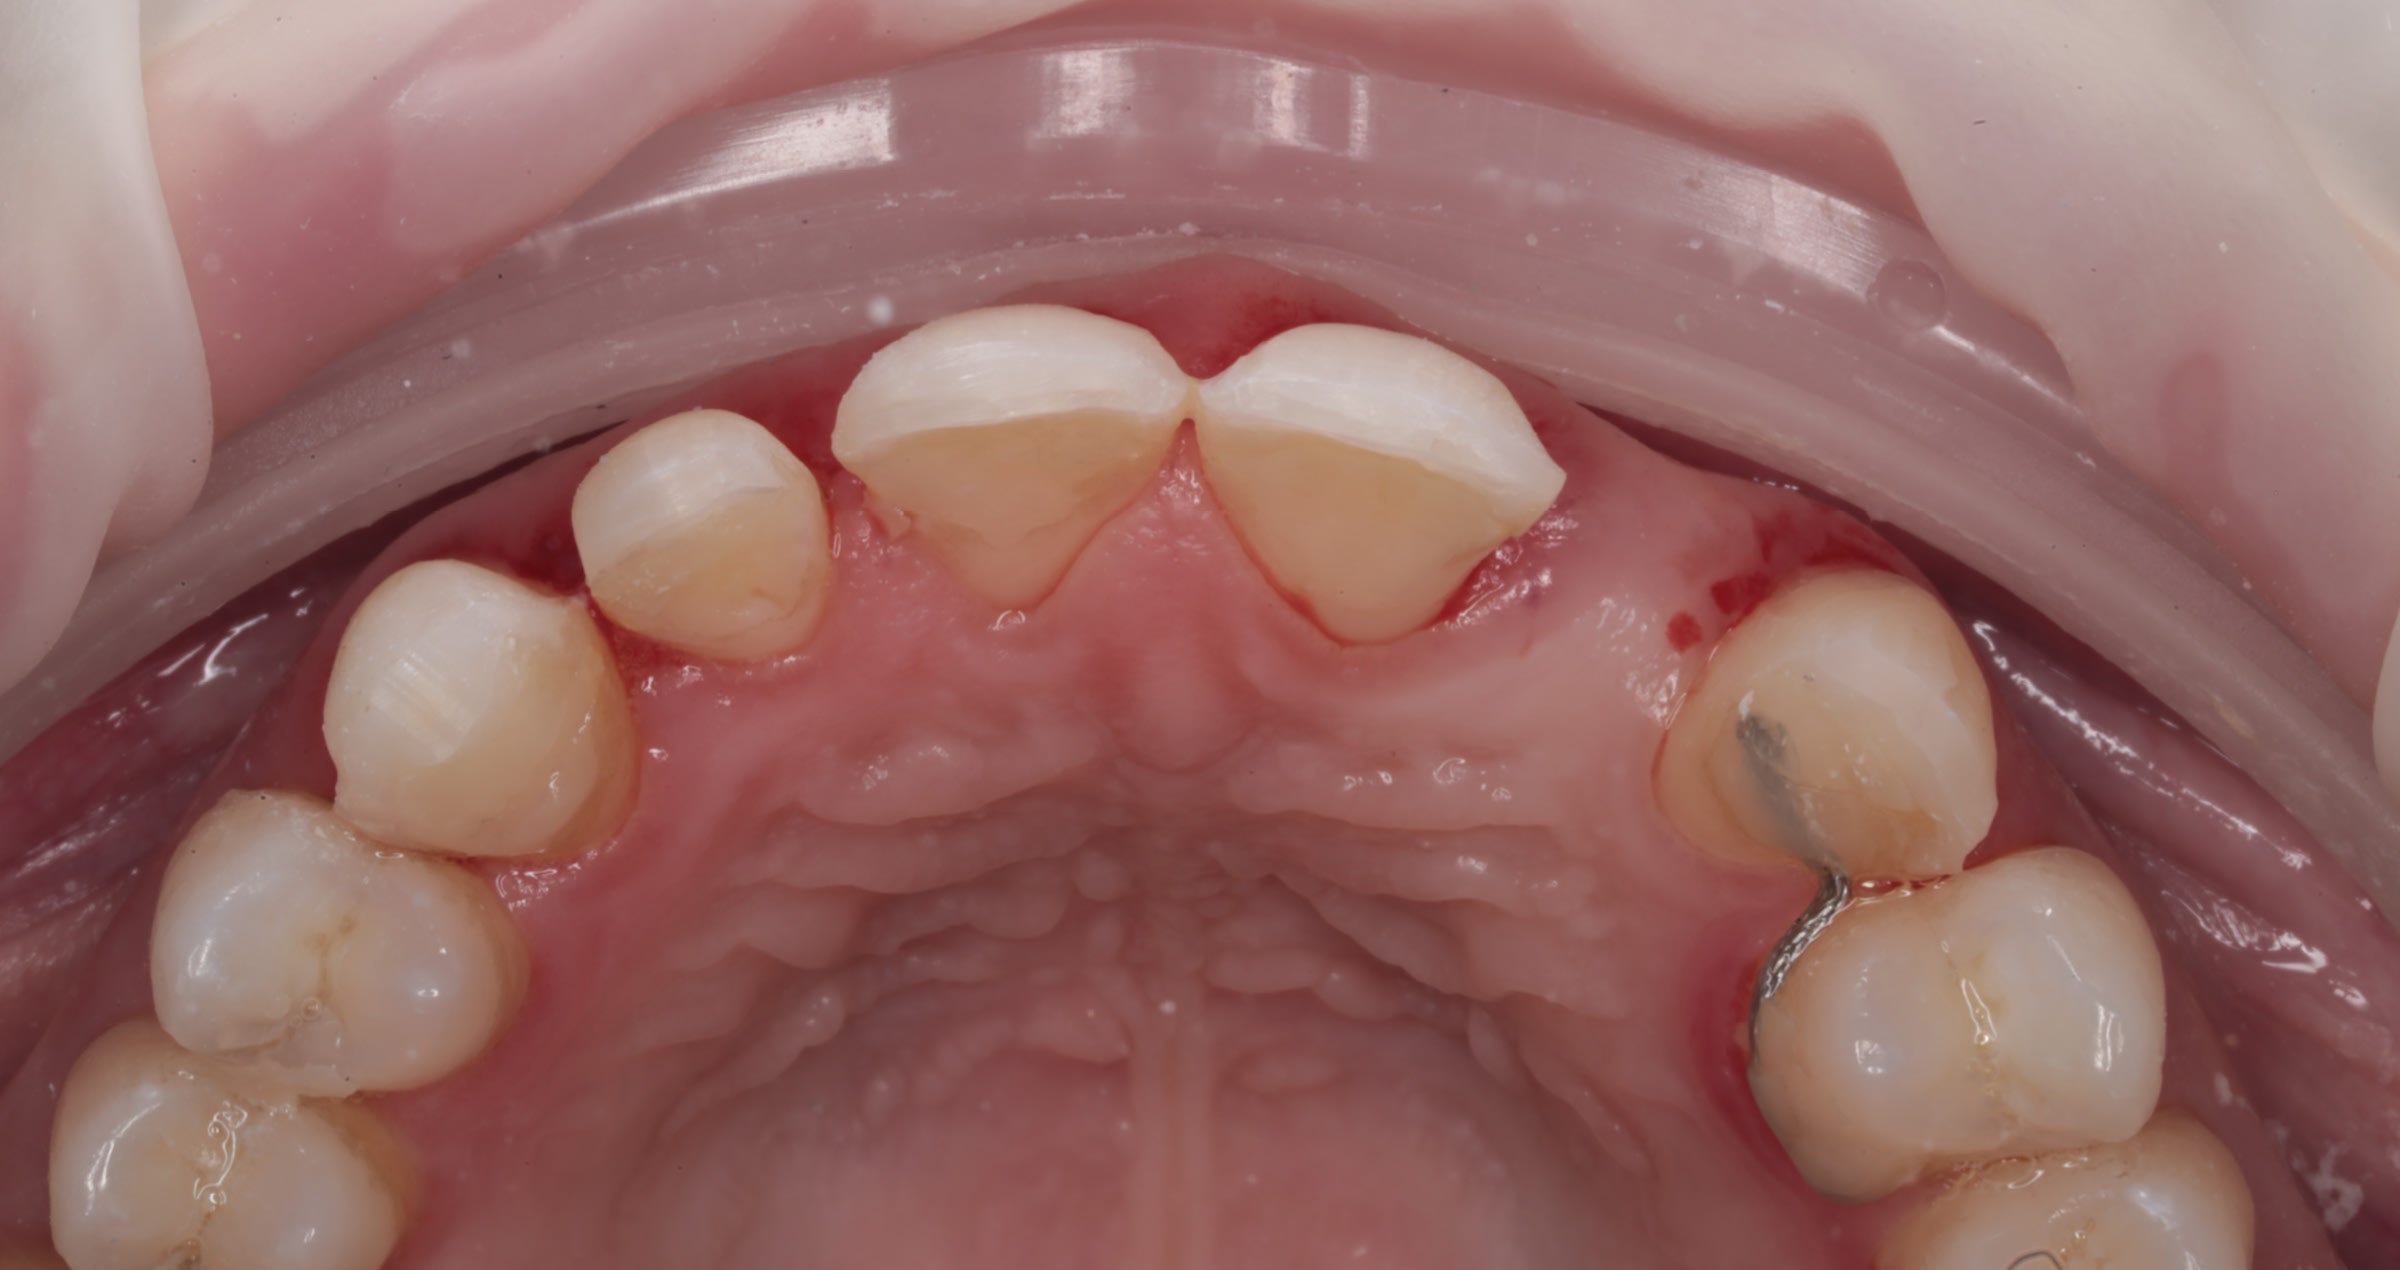

Fig. 6. Occlusal view: Appearance of the restoration after sintering.